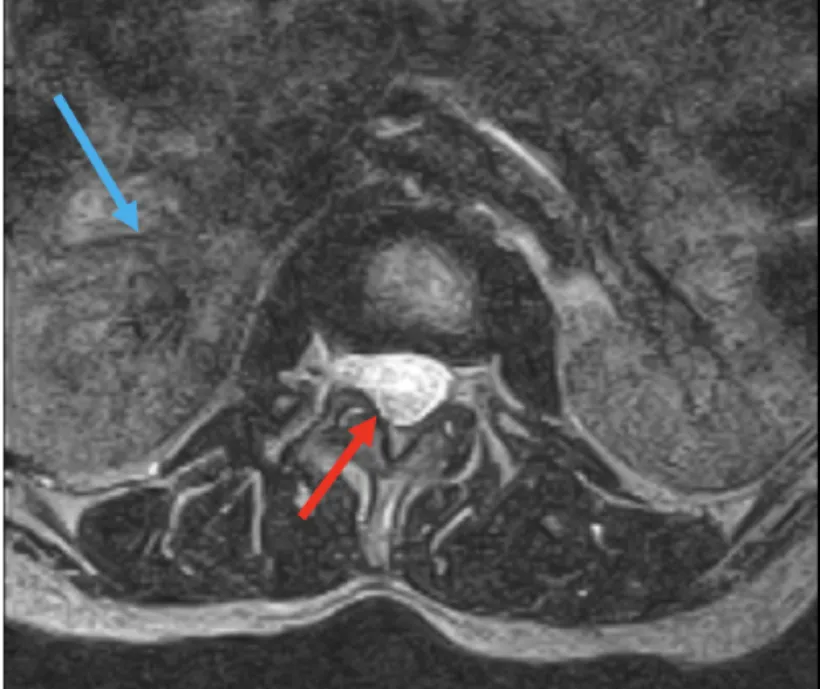

The technical quality of images varies widely from one device to another.

Slide the circle left or right to see how two scanners produce images of the same patient.

In the lower quality image, individual nerve roots and solid organ tissue are difficult to see

Nerve Roots

Organ Tissue

low resolution

high resolution